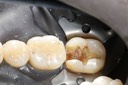

Kyle Chock #2 pre-op